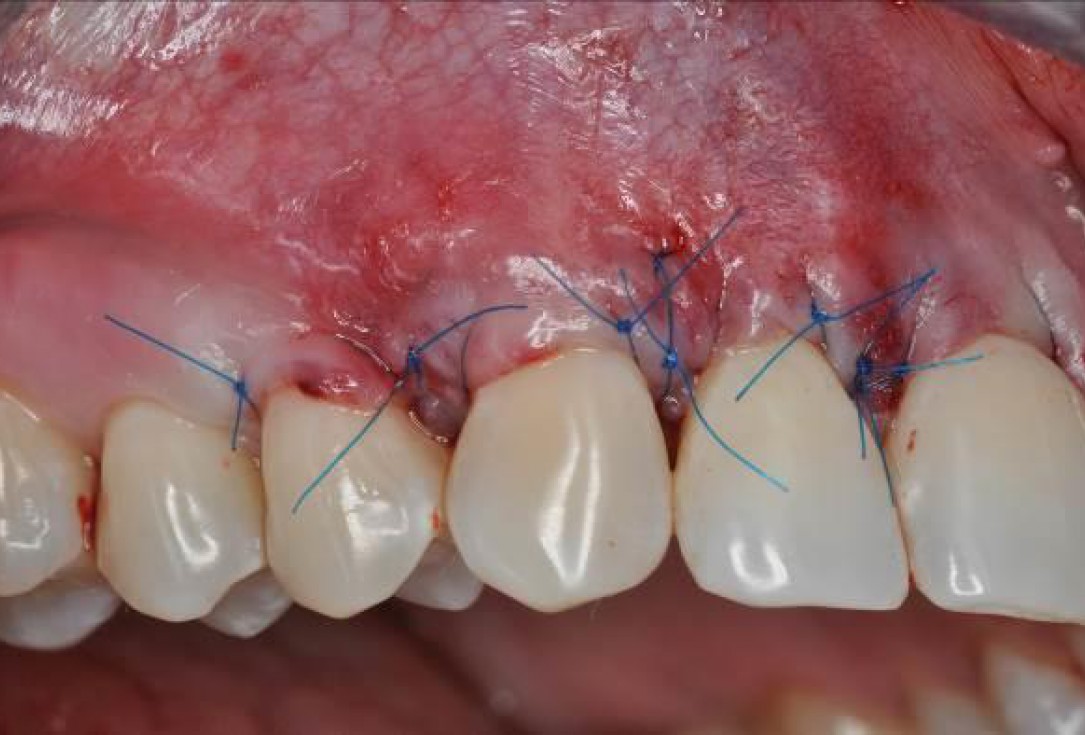

04/06 - Rehydrated mucoderm® placed over the root surfaces and sutured to the wound bed.Multiple gingival recessions treated with the modified coronally advanced flap in conjunction with mucoderm® and Straumann® Emdogain® - Dr. D. B. Hangyási